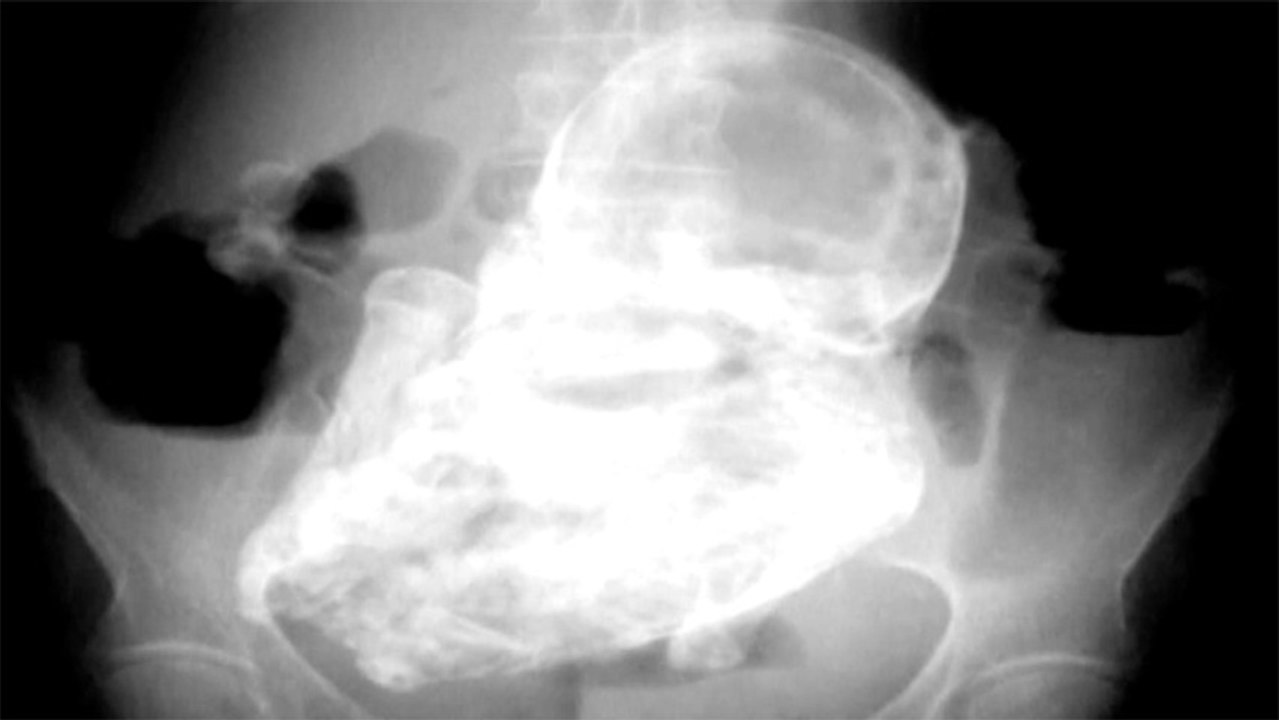

Doctors Discover 40 Year Old Fetus Inside 82 Year Old Woman 1:01

Doctors Discover 40 Year Old Fetus Inside 82 Year Old W...